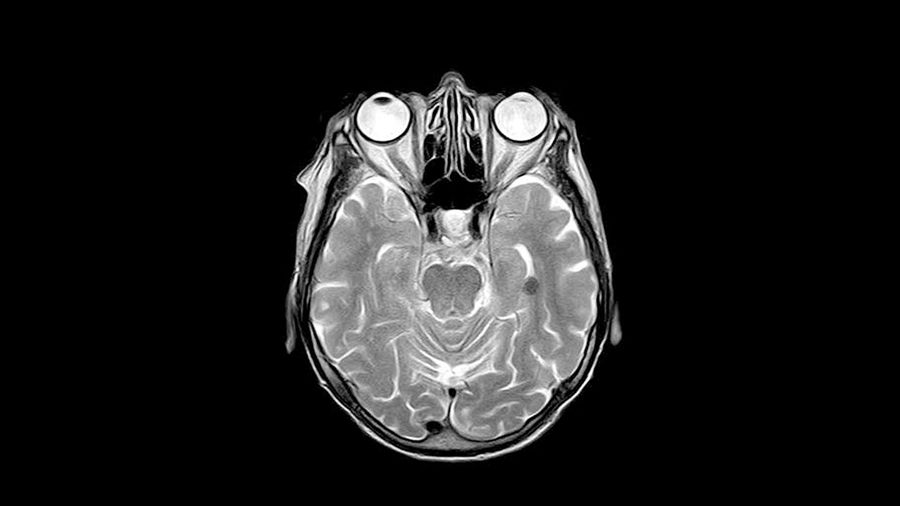

Strålning är det kanske effektivaste verktyget för att behandla elakartade hjärntumörer. Men strålningen ger samtidigt ofta upphov till svåra sena komplikationer, som svårigheter med inlärning och minne och nedsatt intellektuell förmåga, i synnerhet hos barn.

I en ny artikel som publiceras i den vetenskapliga tidskriften Cell Reports beskriver forskare hur effekterna av strålning av en ung hjärna skiljer sig från en vuxens.